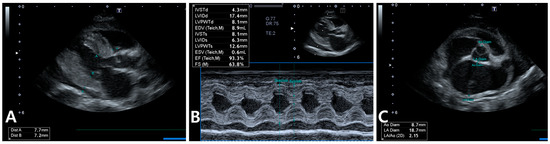

2. Case Description